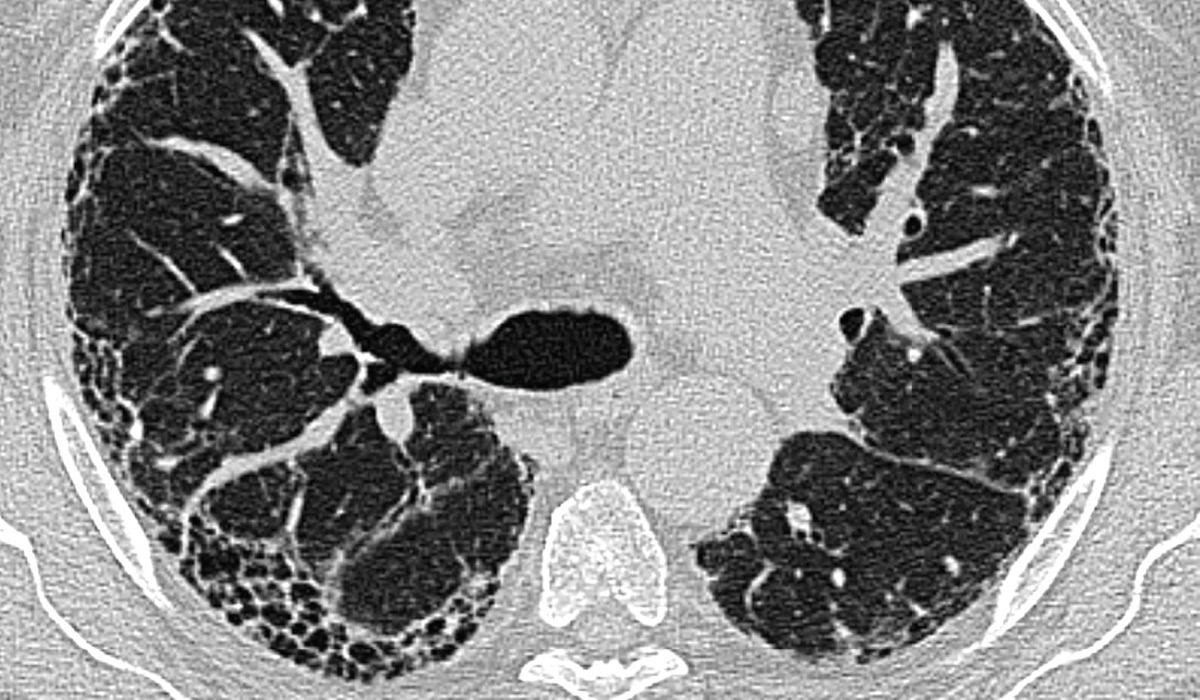

Das Ausmaß der Fibrose, gemessen durch HRCT, ist ein starker, unabhängiger Prädiktor für die Mortalität sowohl bei IPF als auch bei PPF.

HRCT-Bild mit freundlicher Genehmigung von Priv.-Doz. Dr. Hilmar Kühl